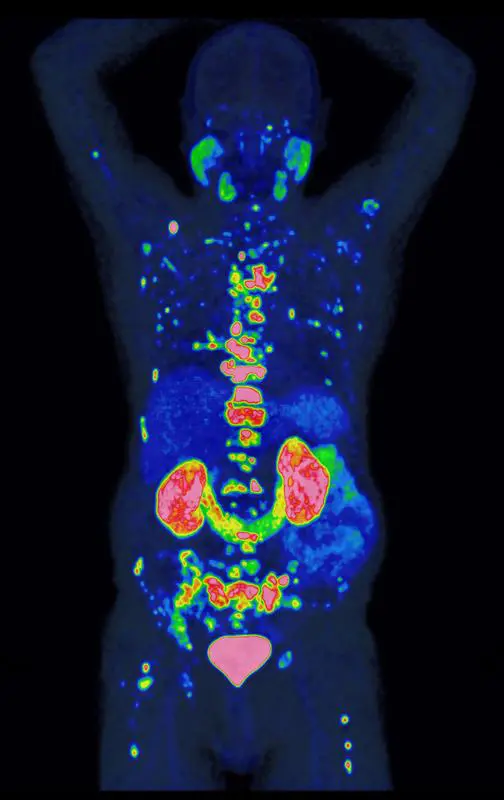

Das PROMISE-Team nutzte für die Risikobewertung die PSMA-PET, ein hochmodernes Bildgebungsverfahren, mit dem sich Prostatakrebszellen besonders präzise und ihr Ausbreitungsstadium im Körper sichtbar machen lassen. Da die Methode empfindlicher ist als ältere Verfahren, mussten ihre Befunde zunächst in neue Behandlungsempfehlungen übersetzt werden – ein Prozess, den PROMISE maßgeblich geprägt hat. In einer der größten Studien weltweit wertete das Team Bilddaten von über 15.000 Patienten aus. Gemeinsam mit international führenden Forschungseinrichtungen entwickelte es daraus das PROMISE-Schema – eine Methode, mit der sich individuelle Risikoprofile auf Basis der PSMA-PET deutlich präziser bestimmen lassen. Darauf aufbauend entstanden Nomogramme, also Vorhersagemodelle für das individuelle Risiko, die für Ärzt:innen und Patient:innen verständlich aufbereitet und zur gemeinsamen Therapieentscheidung nutzbar sind.